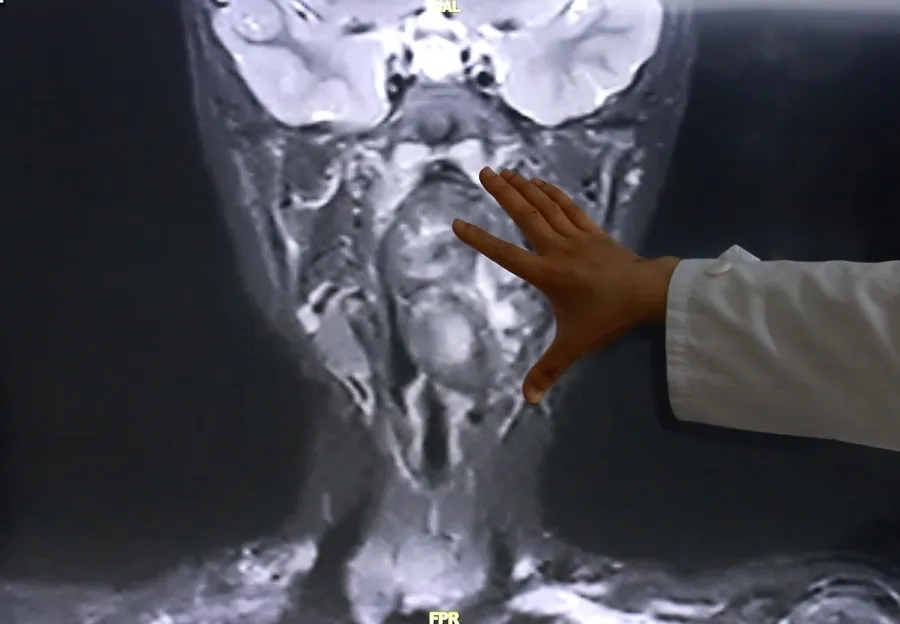

接诊后,综合前期检查及患儿家长自述病情,复旦儿科专家团队高度重视气道梗阻风险,立即启动复杂气道疾病绿色通道,完善增强CT及磁共振检查,明确小亮所患的肿瘤约7×3.5×3厘米,犹如“拳头”般大小。

专家表示,该肿瘤紧邻颈内动静脉并将血管明显向外推移,肿瘤向咽喉腔内隆起,占据大部分口咽及下咽腔,严重压迫声门,随时可能发生窒息。

陈超还表示“6岁男孩的口咽腔大概在8公分左右,这个孩子的肿瘤已经高达6公分多,整个气道已经完全被这个膨大的肿瘤占据了,只有一条黑颜色的线,这是它透气的空间,再让它继续膨胀下来,它首先出现的一个症状应该是呼吸道的梗阻窒息,会出现窒息致死的可能。”